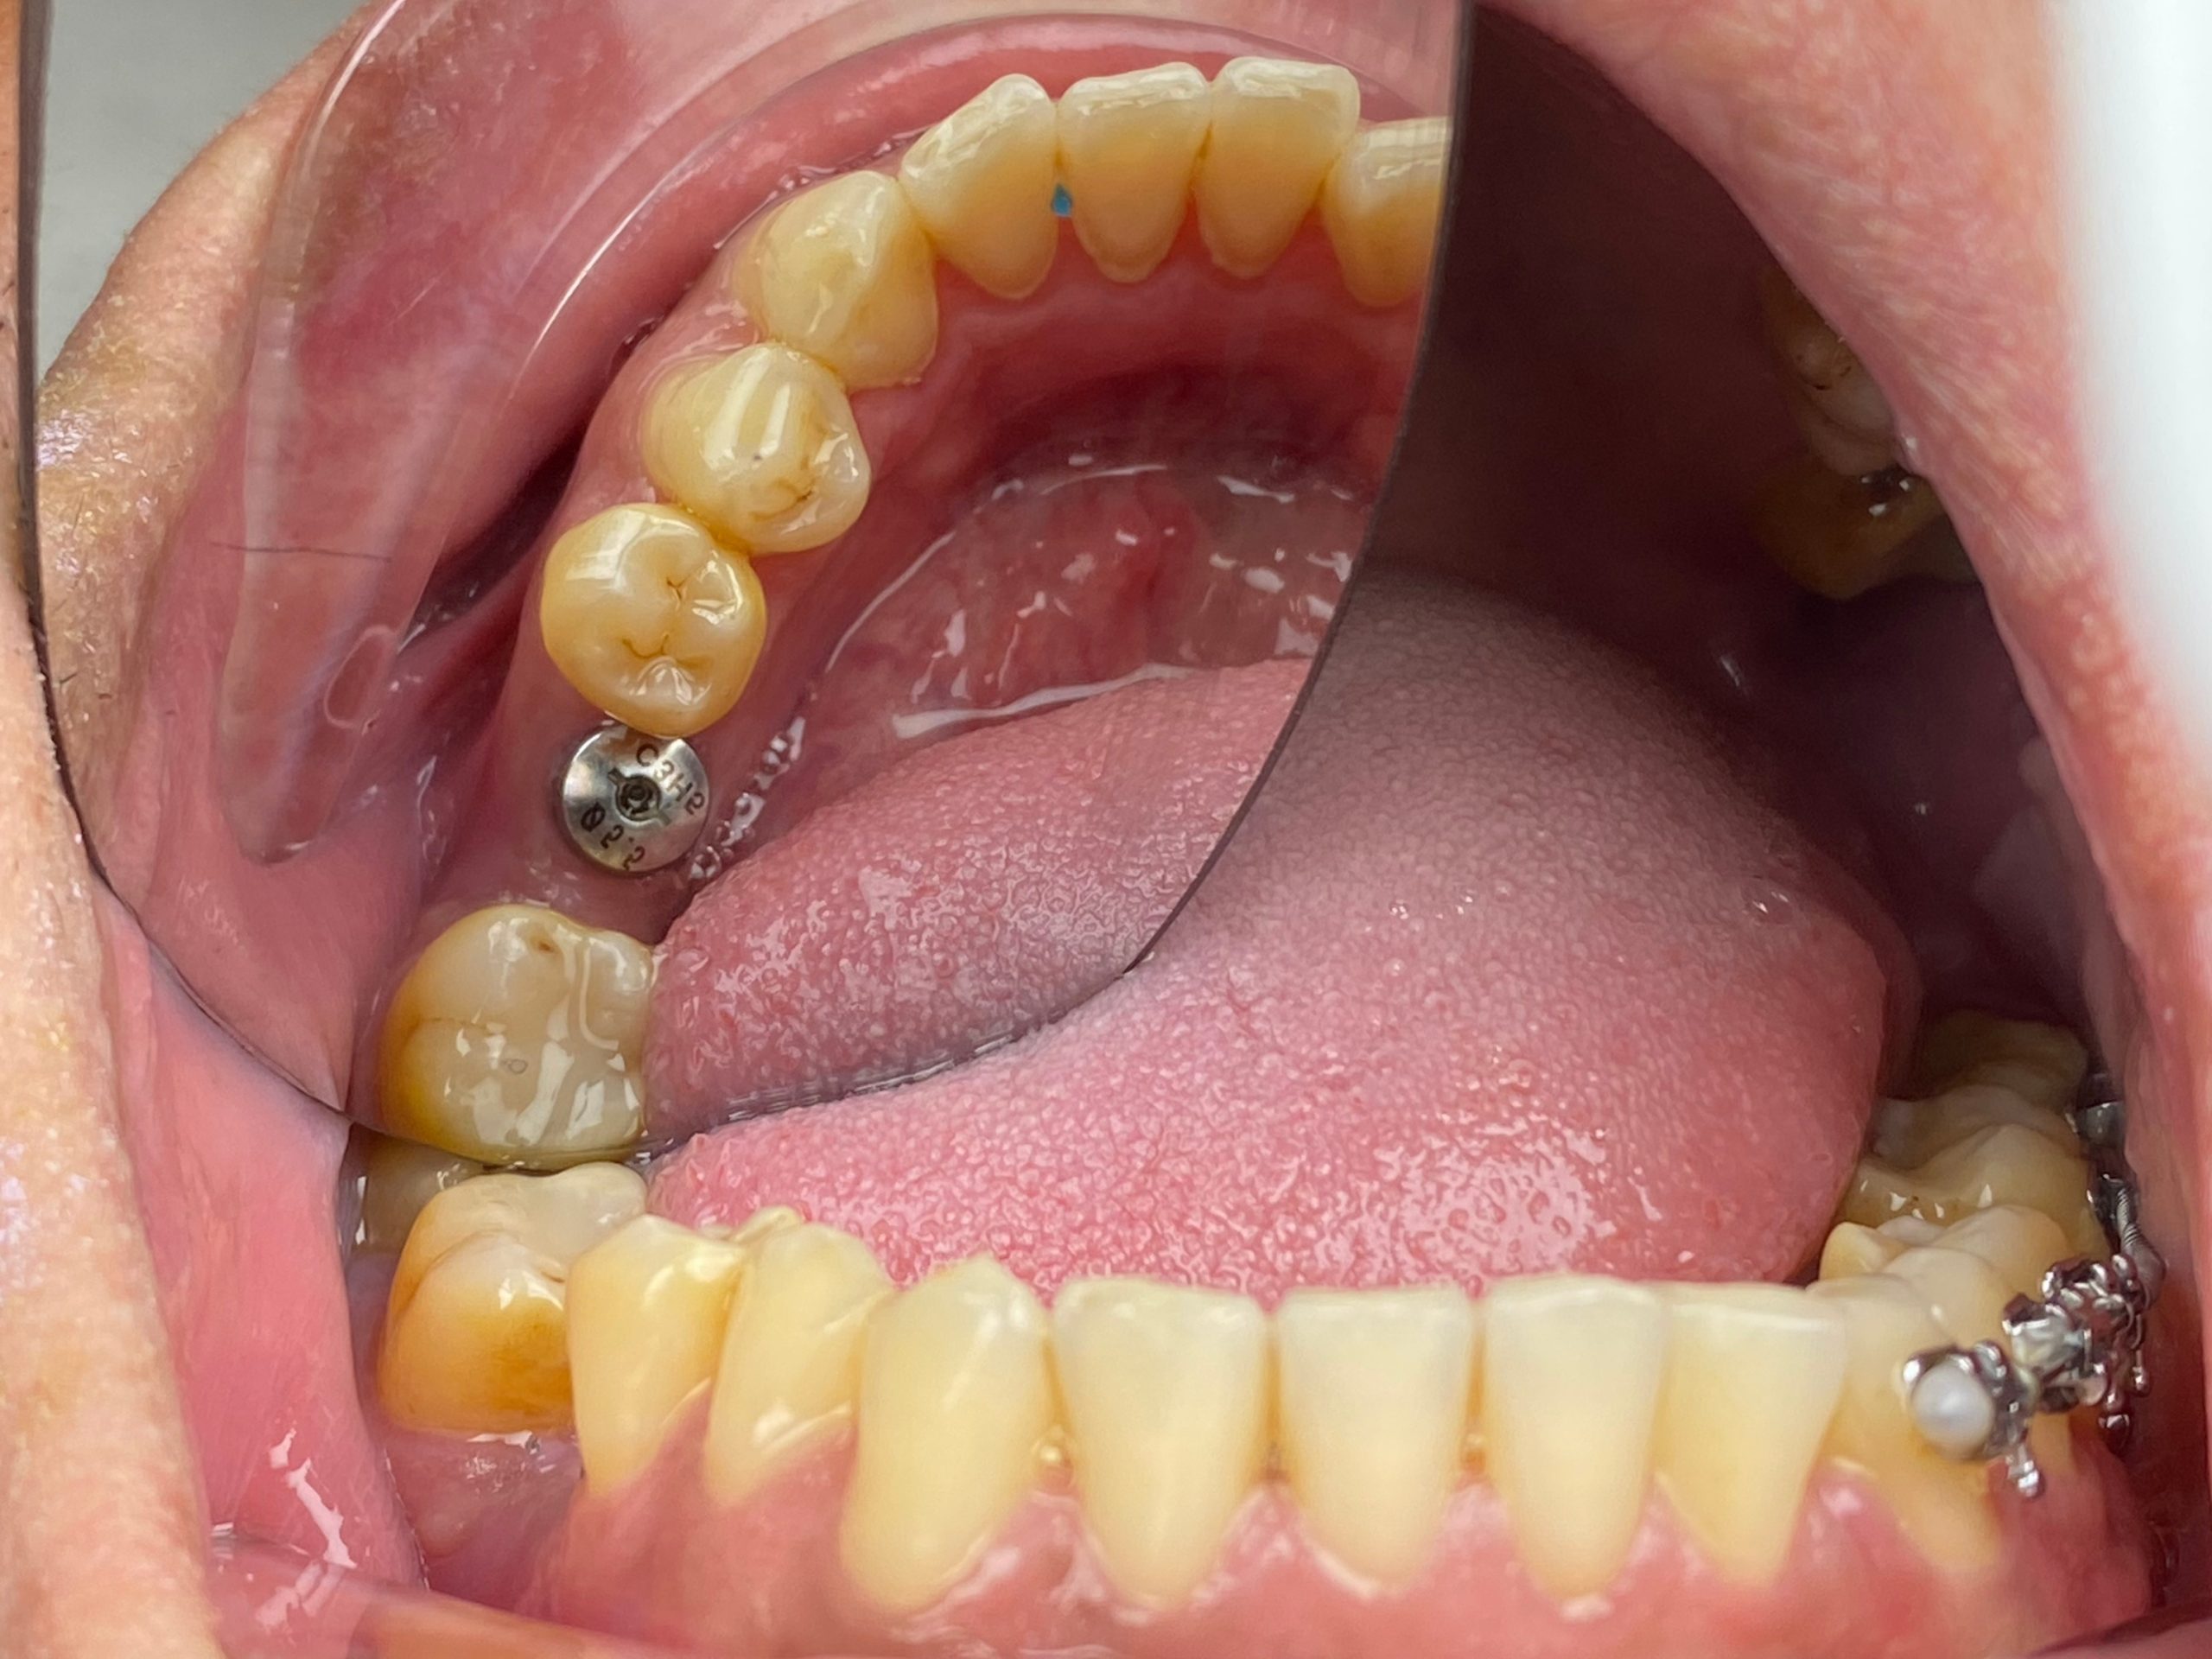

Bước 5: Phục hình răng sứ trên Implant

Sau khi phẫu thuật đặt trụ Implant, cần thời gian để trụ này tích hợp hoàn toàn với xương hàm (thông thường khoảng 6 tuần – vài tháng). Trong thời gian chờ đợi, bác sĩ sẽ lấy dấu răng và gửi về xưởng để chế tác răng sứ. Mão răng sứ được thiết kế cá nhân hóa cho từng người sao cho hình dáng hài hòa, màu sắc tự nhiên, tối ưu nhất về mặt thẩm mỹ.

Khi trụ đã hoàn toàn tích hợp tốt, răng sứ đã chế tác xong thì răng sứ sẽ được gắn cố định lên trụ thông qua khớp nối abutment. Chức năng ăn nhai và thẩm mỹ được khôi phục hoàn toàn. Đây là bước hoàn thiện một chiếc răng hoàn chỉnh trong quy trình cấy ghép Implant.